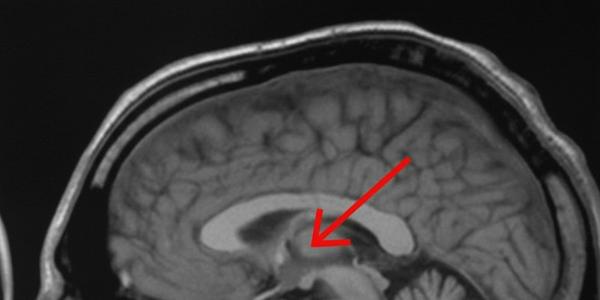

Ученые из Флориды выявили нейронный «таймер» в мозге для координации движений

В США специалисты Института нейробиологии Макса Планка (Флорида) выяснили, как мозг выстраивает последовательность движений с точностью до секунды. Работая с лабораторными мышами, они обнаружили,...